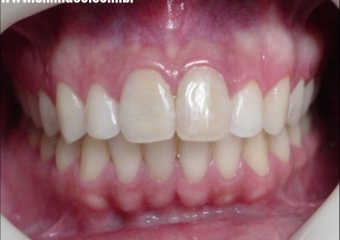

Próteses finais em porcelana

Sorriso final do caso terminado em julho de 2005